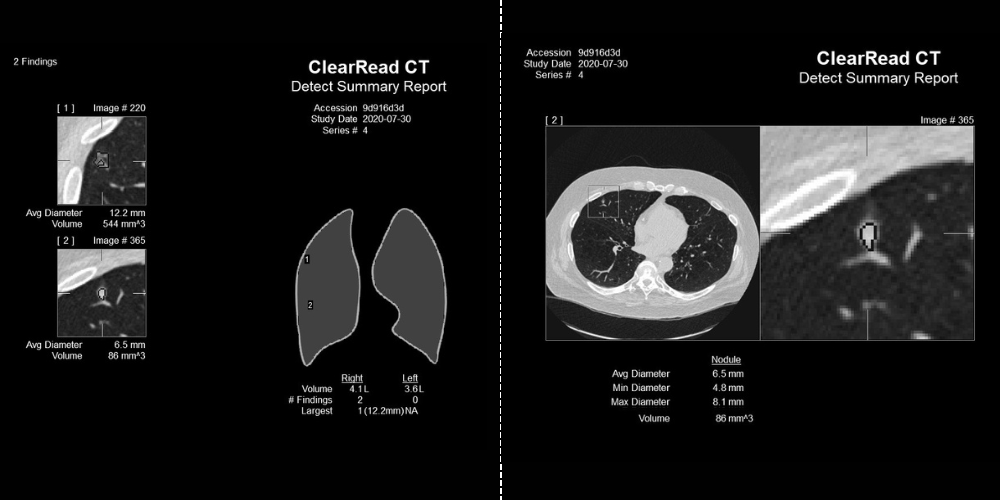

Pulmonary Nodules Automated nodule analysis, current and prior, and reporting to lighten cognitive load

- Fully-automatic nodule detection and analysis

- Quickly & easily compare nodule findings with prior exams – monitor changes in volume, diameter, and doubling time